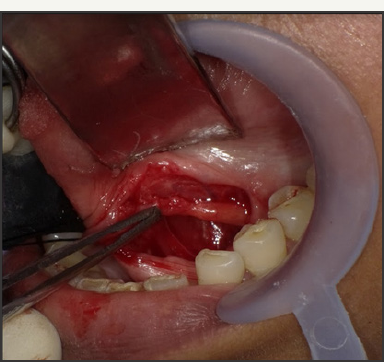

After appropriate preparation and draping, a mouth prop was inserted on ipsilateral side and tongue retracted with a suture. An incision was given with an imaginary line running across the duct with a lateral inclination anteriorly and medial inclination posteriorly. This is done to oppose the path of lingual nerve which is exactly opposite to the incision line, i.e. lingual nerve crosses the duct from below, lateral to medial, in premolar-molar region. A combination of blunt and sharp dissection was used to expose the anterior duct. The point of lingual nerve traversing the duct was identified and lingual nerve protected. Duct was further dissected posteriorly. However, the ductal stone could not be visualised. On applying extraoral pressure to push the deeper part of duct intraorally, the sialolith was seen. Duct posterior to the obstruction was edematous. As an incision was given in the duct over the stone, a spurt of pus threw the stone out (Figure 10 & 11). Gland was further milked and resulted in expression of more pus. Milking was continued till normal salivary flow was observed. The floor of mouth was sutured with 4-0 resorbable suture. Patient was kept on broad spectrum antibiotics and discharged after 2 days. Recovery was uneventful. However, salivary flow was close to nil for about 3 weeks. Patient has been followed up for around 8 months. Some part of the gland has become fibrosed and salivary flow has increased but still less as compared to opposite side.

Figure 10: Operative picture showing the incised part of the duct.